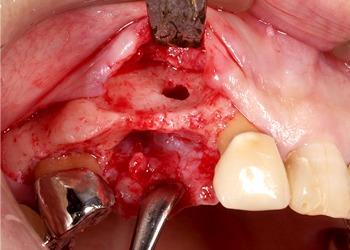

歯肉を開くと大きく骨が吸収しているため、インプラント埋入と同時にGBR